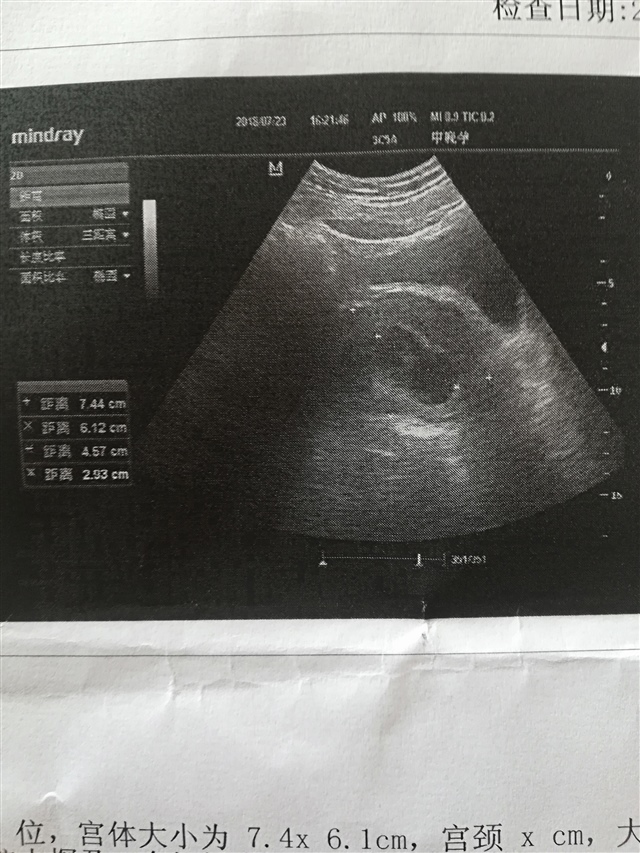

孕17周+5天

正常的